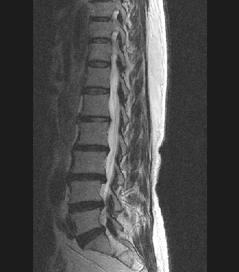

• 척추 방사선 사진1

64세 여자환자는 2개월 전부터 요통과 다리 바깥쪽과 발등, 종아리 뒤쪽으로 저린 감각이 심해져서 개인병원에 들러 평가 및 물리치료를 받았으나 별다른 호전이 없고, 1주일 전부터는 허리를 숙이거나 물건을 들 때, 오래 걸을 때 통증이 더 심해져서 본원을 방문하였다. 12년전 집안일을 심하게 하고 난 후부터 간헐적인 요통을 발생하였으며, 별다른 치료 없이 지냈으며, 4년전 무거운 물건 들고 난 후 심하게 요통과 둔부의 통증까지 발생하여 MRI 촬영상 L1-2, L3-4-5, L5-S1 HNP와 Lt. L4 & both L5 nerve compression, Lt. S1 nerve compression 진단받고 Epidural steroid injection을 받고 통증 경감되었고, 간헐적으로 통증이 발생하였으나 별다른 치료 없이 헬스클럽에서 지속적인 운동으로 관리하였다.